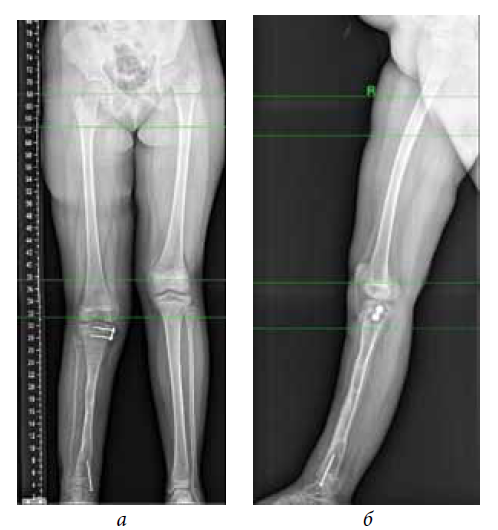

The second stage of treatment was the recommended correction of the resulting multiplane deformities of the affected lower extremity (mMPTA was 94°, mLDTA was 71°, aPPTA was 90°, and aADTA was 59°, shortening the affected lower limb by 8.0 cm). For lengthening and deformity correction of the right lower limb, the patient underwent preoperative planning for deformity correction with the exception of osteotomies in the area of consolidated pseudoarthrosis at the age of 9 years. According to the plan, a two-level osteotomy of the shin bones was performed, as along with lengthening by 5 cm by the Ilizarov method. The deformity was corrected using a repositional unit with Ortho-SUV computer navigation properties. The period of deformity correction was 58 days, and the external fixation period was 247 days. At the end of the fixation period, a recurrence of deformities of the tibial bones was detected with the formation of a deformity apex at the level of the proximal and distal tibial growth zones (mMPTA was 94°, mLDTA was 82°, aPPTA was 86°, and aADTA was 80°) (Fig. 1–4). We applied hemiepiphysiodesis to correct the recurrence of valgus deformity of the tibia. The period of deformity correction was 269 days. The reference angles values of the tibia were within the accepted ranges.

Fig. 1. Photograph of the patient with cCPASB prior to deformity correction: а — аrontal view; b — lateral view

Fig. 2. Radiographs of the patient with cCPASB prior to deformity correction: а — anterior-posterior view; b — lateral view